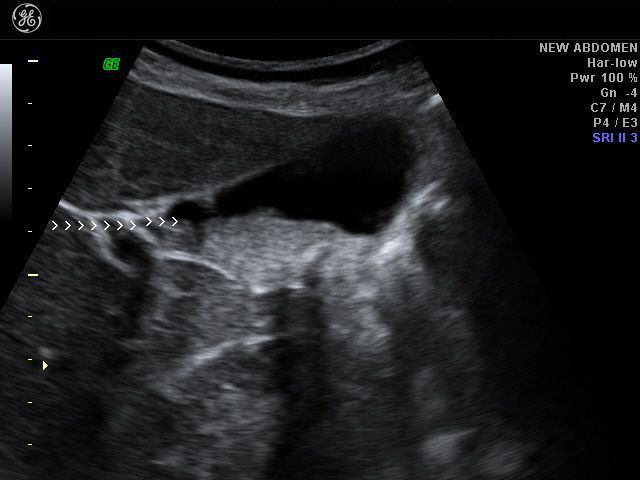

case-2: thick GB sludge causing hepatization of gallbladder- 3D ultrasound images

Sonography of the right hypochondrium shows a large distended gall bladder with markedly echogenic contents. The echogenicity appears similar to that of the liver (hepatization of the gall bladder). This ultrasound image suggests presence of limy bile in the gall bladder. This is caused by the collection of calcium rich salts within the organ and is an extreme form of biliary sludge. It is also known as Milk-of-calcium bile and is often associated with cholecystitis. Ultrasound image (upper most row- case-1) is courtesy of Prasenjeet Singh, MD, India. This image was taken using a Toshiba Nemio -30 system.

case-2: shows hepatization of gallbladder. Using a Samsung Accuvix ultrasound system.